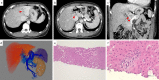

A 42-year-old woman visited our hospital due to syncope. Contrast-enhanced CT revealed portosystemic shunt, portal vein hypoplasia, and multiple liver nodules. The histological examination of a liver biopsy specimen exhibited portal vein hypoplasia and revealed that the liver tumor was positive for glutamine synthetase. The patient was therefore diagnosed with congenital extrahepatic portosystemic shunt type II, and with focal nodular hyperplasia (FNH)-like nodules. She had the complication of severe portopulmonary hypertension and underwent complete shunt closure by balloon-occluded retrograde transvenous obliteration (B-RTO). The intrahepatic portal vein was well developed at 1 year after B-RTO, and multiple liver nodules completely regressed. Her pulmonary hypertension also improved.